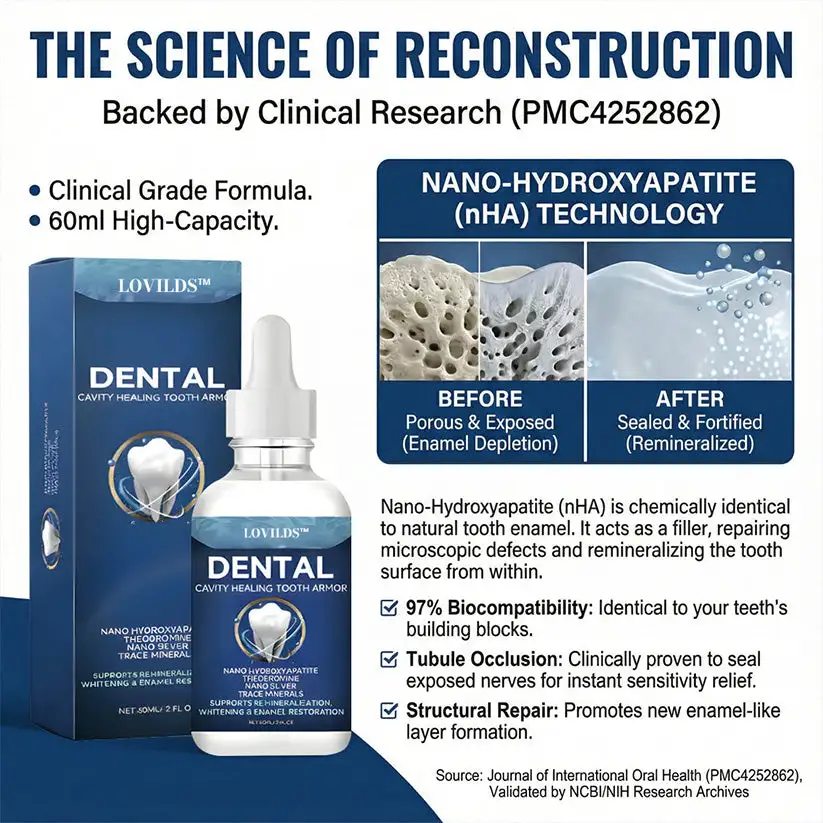

Standard dental care often focuses solely on cleaning the surface. Teeth Armor Drops go deeper by addressing the microscopic mineral loss that leads to discomfort and surface irregularities. By integrating Nano-Hydroxyapatite (nHA), our formula supports the natural remineralization process, helping you maintain the structural integrity of your teeth without invasive procedures.

The Science of Structural Support

Traditional methods often wait for issues to become visible before acting. Our serum is a proactive wellness tool designed to intervene during the “silent phase” of mineral depletion.

How Nano-Hydroxyapatite Transforms Your Smile

Micro-Filling Technology: Acts as a biological filler to smooth the tooth surface, leaving your teeth feeling “polished-glass” smooth.

-

Mineral Replenishment: Delivers the exact building blocks your enamel needs to stay strong and resilient against daily acids.

Protective Barrier: Creates a long-lasting shield that neutralizes environmental stressors for hours after application.